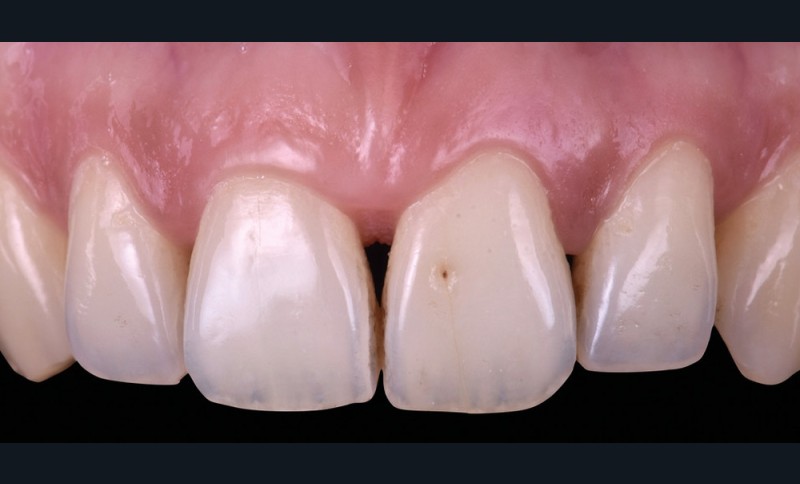

Les triangles noirs

Ils correspondent à une perte de papille interdentaire et sont principalement observés :

– lorsque la distance point de contact/crête osseuse est supérieure à 5 mm ;

– chez des patients présentant une atteinte parodontale avec une perte osseuse associée à une récession horizontale ;

– pour des dents le plus souvent de forme triangulaires ;

– en post-traitement orthodontique.